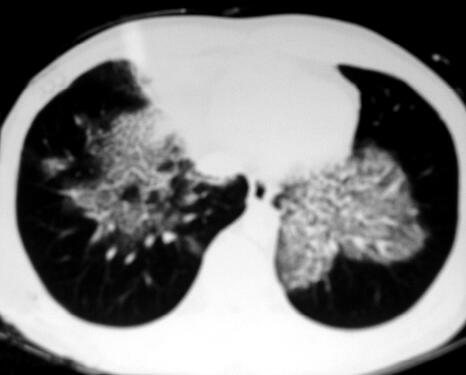

10.胸部影像学:双肺多发斑片影(图1)。

图1

重要的检查结果有四项:①血常规:白细胞总数、中性粒细胞比率均略增高;②胸部影像学:胸部CT示双肺以肺门为中心对称的斑片影;③肺功能:FVC、FEV1均减低,FEV1/FVC%正常,DLCO:74%预计值。④血气分析:PaO2 62mmHg,PaCO2 34mmHg,P(A-a)O2 41mmHg。